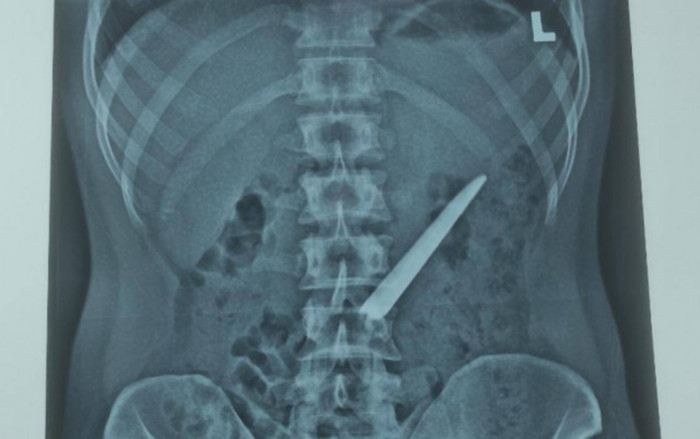

Hình ảnh chụp X-Quang cho thấy lưỡi dao nằm trong bụng bệnh nhân. Ảnh: Báo Giao Thông

Sau khi thăm khám và nội soi, các bác sĩ phát hiện một vật sắt nhọn dài khoảng 10cm (lưỡi dao Thái Lan không có cán) nằm bên trong bụng đoạn giữa tá tràng.

Sau khi chẩn đoán, các bác sĩ đã tiến hành phẫu thuật hở. Sau gần 1h phẫu thuật, dị vật đã được gắp ra ngoài thành công.